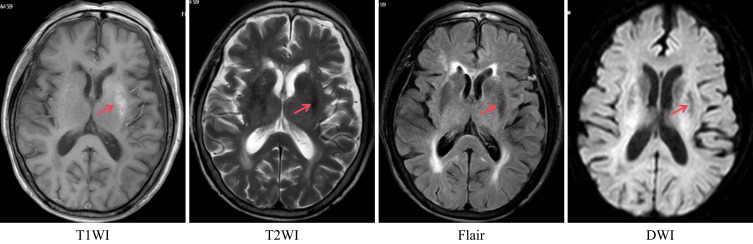

Case presentation: We report two patients undergoing regular hemodialysis for end-stage renal disease who presented with progressively intensified involuntary limb movements. Treatment with sedatives alone proved ineffective in both cases. Through differential diagnosis, one patient was diagnosed with diabetic striatopathy and managed with intensive glycemic control, while the other was found to have uremic metabolic encephalopathy and treated with a combination of hemodialysis and hemoperfusion. Subsequently the patients' symptoms improved significantly.